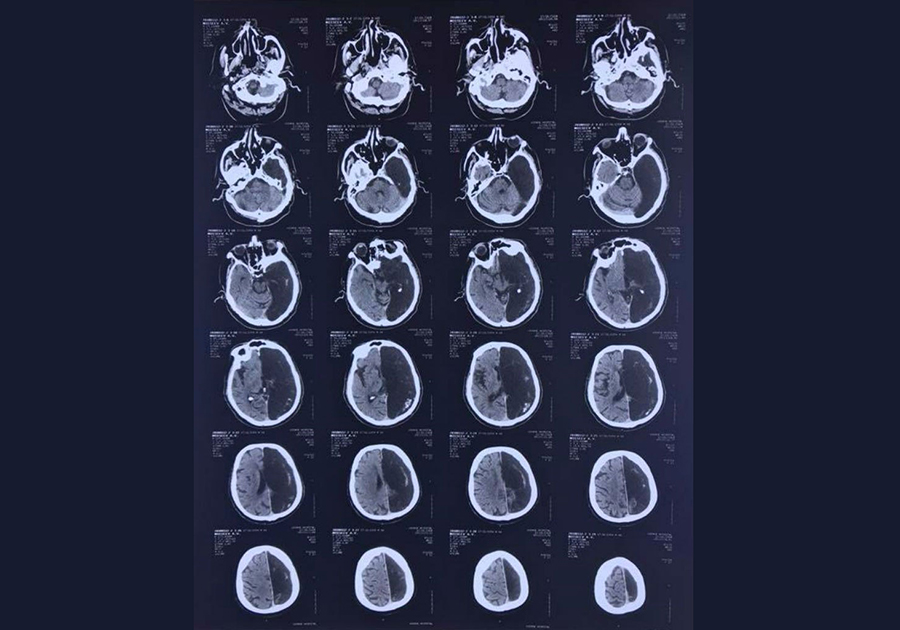

Врачи из Подмосковья столкнулись с аномалией - у поступившего к ним пациента было обнаружено отсутствие одного полушария мозга. Как рассказала журналистам невролог Федерального центра экстрапирамидных заболеваний и психического здоровья ФМБЦ им. А. И. Бурназяна Марина Аникина, 60-летний мужчина был доставлен в больницу из-за возникшего у него нарушения кровообращения головного мозга - транзисторной ишемической атаки, вызвавшей проблемы с подвижностью руки и ноги. Пациенту была сделана КТ (компьютерная томография), и сканирующая техника показала: у пациента наличествует лишь одно правое полушарие мозга.

Врачи пошли навстречу пациенту и после улучшения его состояния простились с ним без проведения дополнительных процедур по изучению мозга. Специалисты пришли к выводу, что функции всего мозга у этого человека на протяжении жизни выполняло только оставшееся правое полушарие. Они смогли выяснить лишь то, что у необычного пациента никогда не было проблем со здоровьем, он успешно окончил школу, отслужил в армии, закончил вуз и получил профессию инженера. Личная жизнь мужчины тоже вполне устроена: он женат, в своем браке воспитал двоих детей.